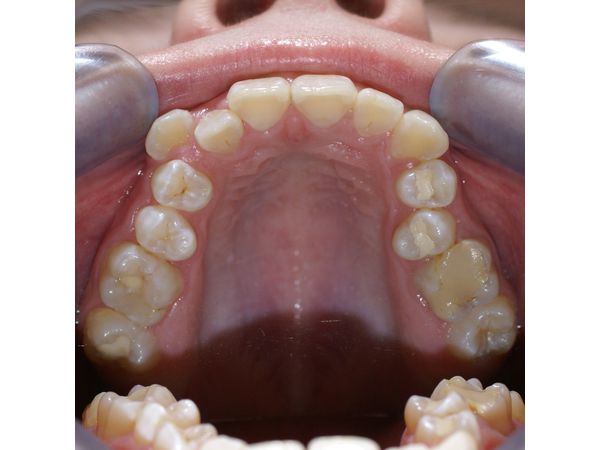

На диагностическом приёме девушке составили фотопротокол, сняли оттиски и изготовили модели челюстей с биометрическим измерением.

Диагноз